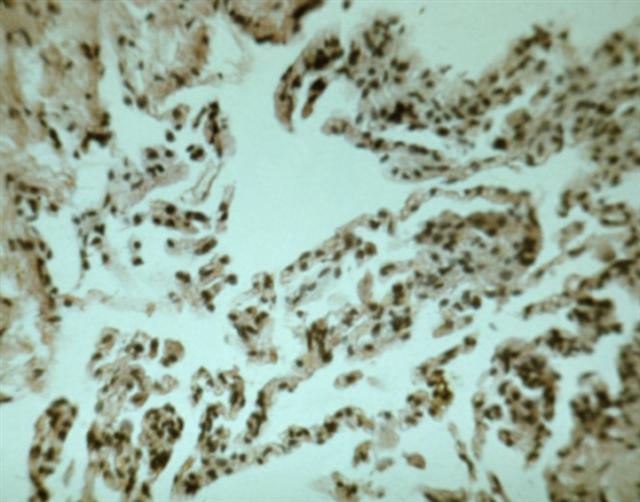

Рис. 1. Микропрепарат легкого при саркоидозном альвеолите (материал биопсии): видна лимфоидная инфильтрация межальвеолярных перегородок; окраска гематоксилином и эозином; ´240.